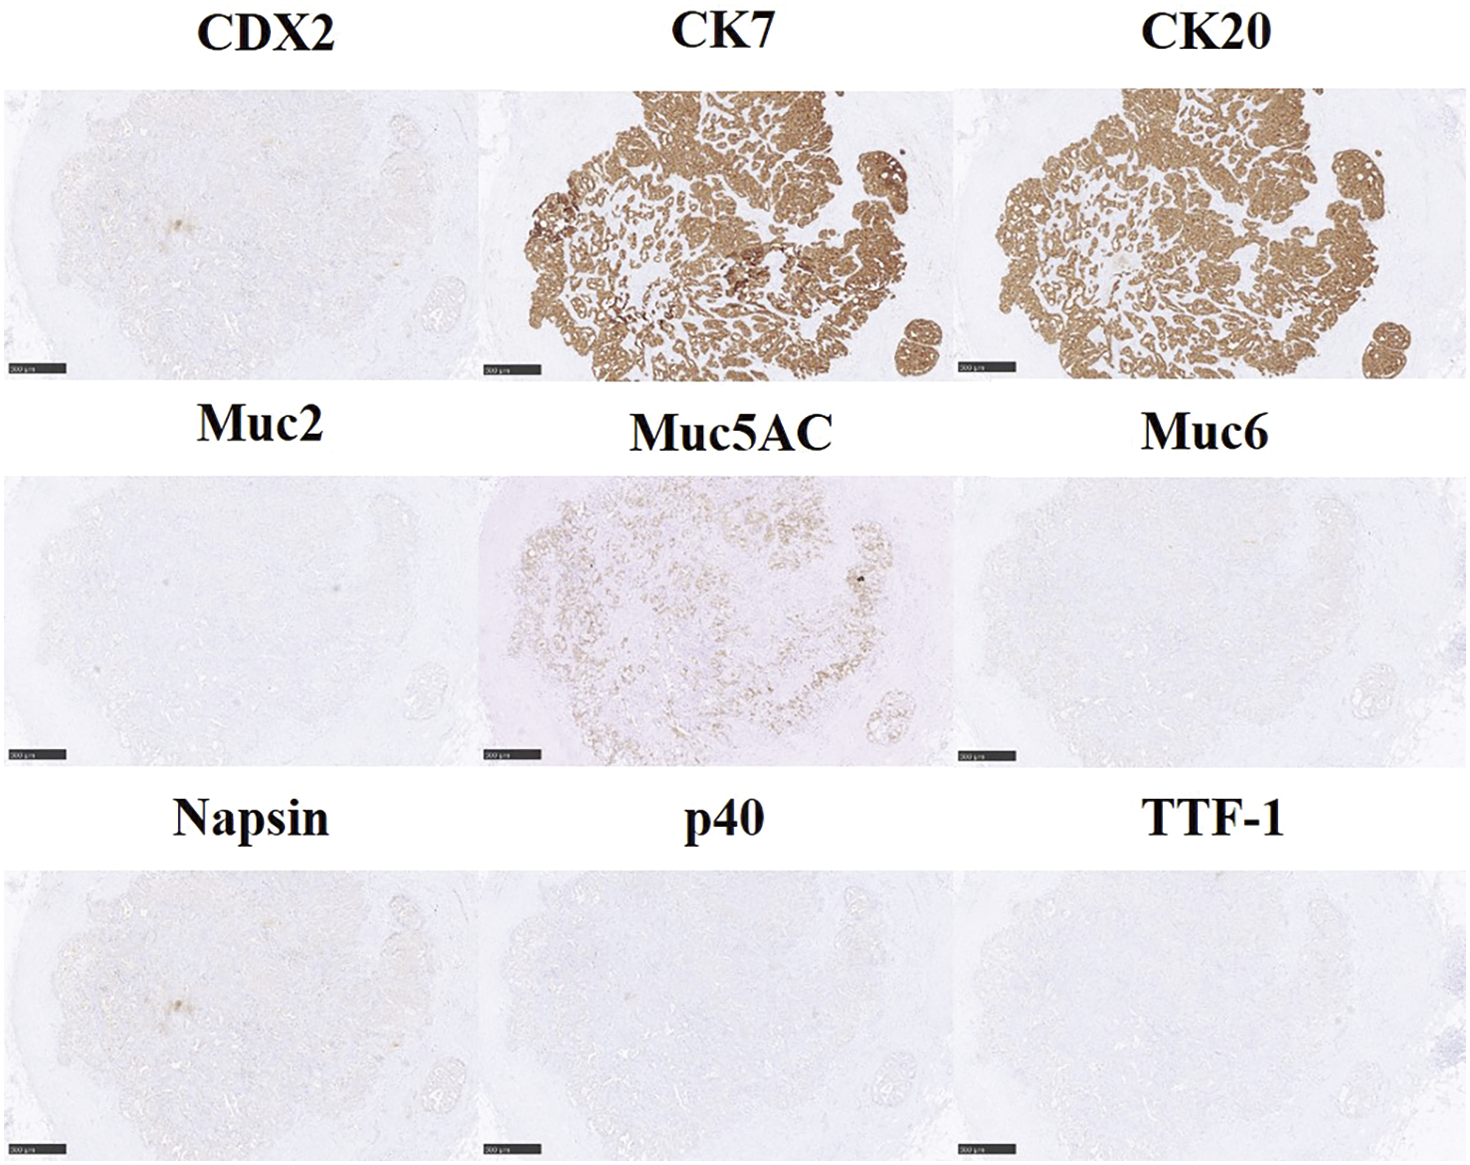

The patient is a 74-year-old man who had surgery for cervical esophageal cancer 2 years ago. The final diagnosis was moderately differentiated squamous cell carcinoma (SCC) with LN metastasis, pT3N1M0 pStage III. Chemoradiotherapy was performed and there was no recurrence of the esophageal cancer. During follow-up, a low-density lesion, a diameter of 15 mm, was detected in segment 4 of the liver by CT (Fig. 1A). The tumor was located just adjacent to the umbilical portion. There were some swollen LNs in the anterior mediastinum (Figs. 1B and 1C). The accumulation of FDG was also detected in the hepatic lesion (standardized uptake value; SUVmax: 8.4) and the anterior mediastinal LN (SUVmax: 11.1) by PET (Fig. 1D). Needle biopsy was performed for the liver tumor and the diagnosis was ICC (Figs. 2A and 2B). The elevation of the serum level of carbohydrate antigen 19-9 (CA19-9) was detected and its level was 119 ng/mL. The levels of carcinoembryonic antigen (CEA) and SCC were within normal range. To confirm the diagnosis of the swollen LNs in the anterior mediastinum, an excisional biopsy was performed. In the operation, there were several firm LNs pulpable just behind the sternum. According to the pathological findings, the tumor in the LN was an intermediate differentiated adenocarcinoma. Atypical cells with increased nuclear chromatin and enlarged nuclei were proliferating and forming glandular structures (Figs. 2C and 2D). The structure of the tumor in the LN was similar to that of the hepatic lesion. Immunohistochemistry showed that the tumor was positive for CK7 and CK20, weakly positive for MUC5AC, but negative for CDX-2, Napsin, TTF-1, and p40 (Fig. 3). The final diagnosis was the lymphatic metastasis from ICC. As the diagnosis of distant metastasis (Stage IVB), the chemotherapy using Gemcitabine, Cisplatin, and Durvalumab was performed for 8 courses. The new lesion appeared just next to the main tumor in S4 (Fig. 4) and the elevation of CA19-9 was also observed (Fig. 5). We could not detect any swollen LNs in the anterior mediastinum by PET or CT. In addition, it was difficult to continue the chemotherapy due to the renal dysfunction. As the tumors were located in the left lobe of the liver, a left hepatectomy with LN dissection was performed. In the operation, there were multiple intrahepatic metastatic lesions limited to the left lobe of the liver. Grossly, the lesion corresponds to a mass-forming type with a central necrotic area and several satellite nodules (Fig. 6). The size of the main tumor was 30 mm in diameter. Most of the tumor cells were viable and they showed serosal and neural invasion around the portal vein (S1, Vp1, Vv0, and Va0). There were no metastases in the regional LNs. Although re-elevation of CA19-9 is observed after hepatectomy (Fig. 5), the patient does not have any recurrence for 9 months after hepatectomy.

Fig. 3

Immunohistochemistry of the lymph node. The tumor of the lymph node was positive for CK7 and CK20 and weakly positive for Muc5AC. Scale bars: 500 μm.